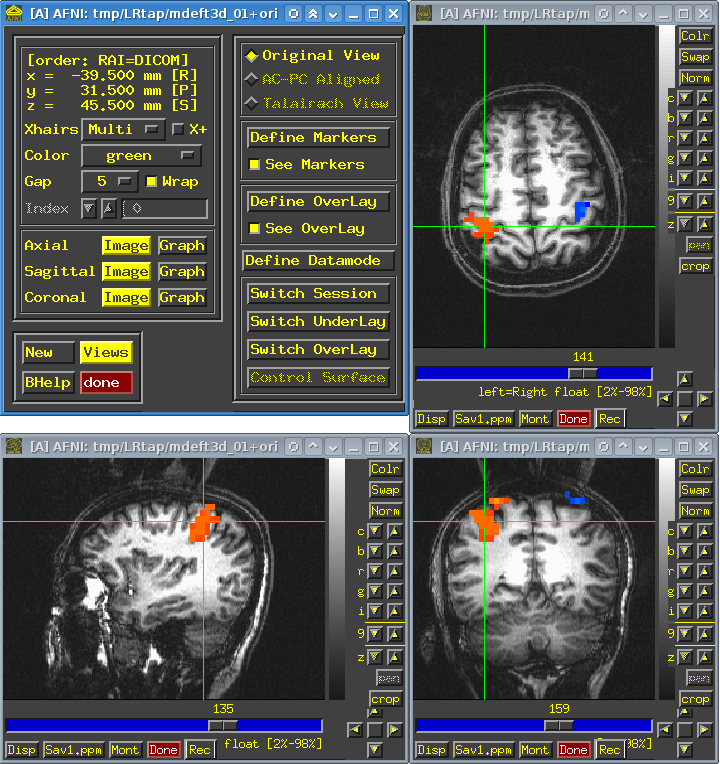

Во-вторых, ошибки в программном обеспечении могут причинять вред и косвенно. Например, баги в программном обеспечении для МРТ-сканеров ставят под сомнение 40 000 научных исследований. В течение нескольких десятилетий нейробиологи и когнитивные психологи использовали для анализа данных фМРТ статистические программы AFNI, SPM и FSL. Как выяснилось, из-за некорректных алгоритмов эти программы могут возвращать до 70% ложноположительных результатов вместо предполагаемых 5%.

Это не абстрактная теоретическая проблема. Я сам сталкивался с ситуацией, когда при переносе программы на 64-битную систему начала проявляться ошибка, приводящая к неправильной обработке МРТ-данных. К счастью, ошибка проявляла себя очень явно: отсутствовал большой фрагмент изображения. Однако ошибка может быть не столь заметной и заключаться в неправильном отображении каких-то мелких деталей, и обнаружить её будет гораздо сложнее.